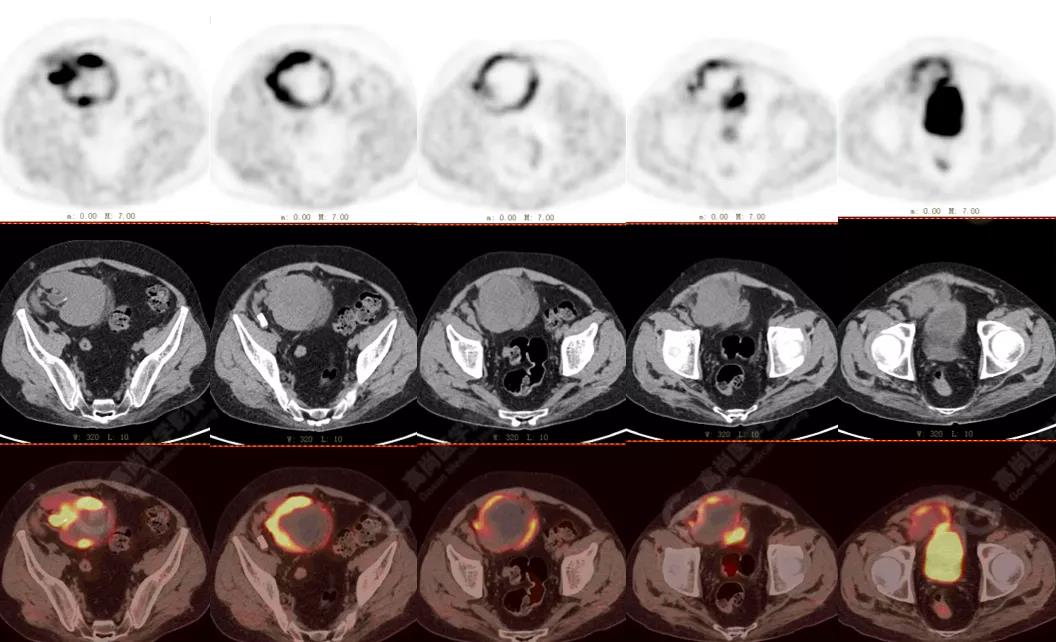

↑移植腎下部等密度腫塊,代謝環(huán)狀增高,SUVmax13.4,中心代謝缺損